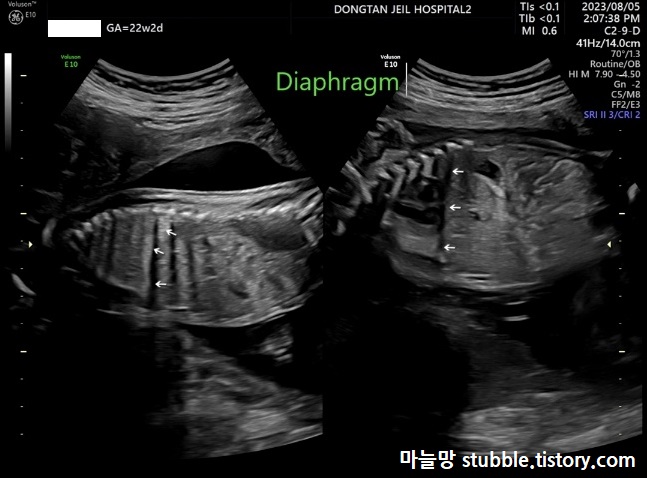

8. 횡격막 잘 형성되어 있는지의 여부 (Diaphragm)

화살표 친 부분이 횡격막입니다.

횡격막도 잘 있는 걸 확인했어요.